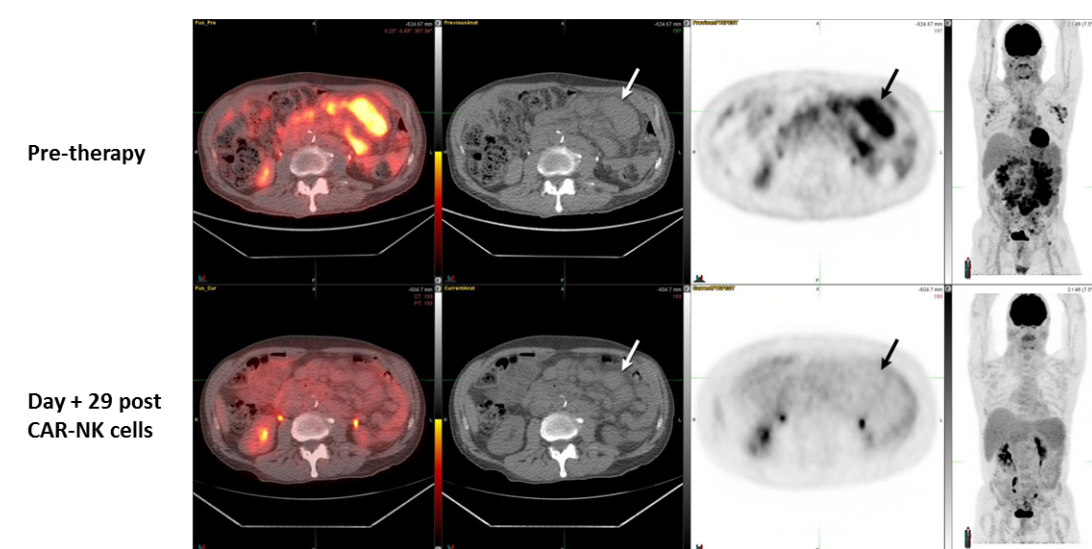

近年来,CAR-T细胞疗法在血液系统肿瘤已经取得显著成就,部分长期治愈的案例震惊众人。受这一成功的启发,研究人员开始将目光转向了NK细胞。NK细胞是被称为自然杀伤细胞,是人体重要的免疫细胞,可以在无需事先致敏的情况下消灭识别和杀死肿瘤细胞。如果为NK细胞设计一款适应NK细胞的CAR的话,那么CAR-NK疗法能否是更强大...